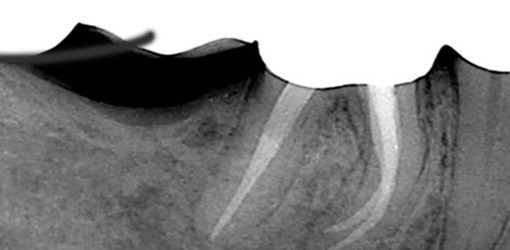

Die Guttapercha und der Sealer wurden vollständig unter kontinuierlicher Spülung mit Chlorhexidindiglukonat 1% und maschinell angetriebenen Nickel-Titan-Feilen (ProFile, Maillefer, Ballaigues) entfernt. Der unbehandelte zweite mesiobukkale Wurzelkanal war stark verengt und konnte erst nach tiefergehender minimalinvasiver Präparation ab dem mittleren Wurzeldrittel vollständig erweitert und desinfiziert werden. Nach einer wiederholten elektrometrischen Messung und röntgenologischen Kontrolle der ermittelten Arbeitslänge (Abb. 9) wurden alle vier Wurzelkanäle vollständig aufbereitet und mittels ultraschall­aktivierter Spülung gereinigt und desinfiziert (Zitronensäure 10% und Natriumhypochlorid 3%) und im Anschluss thermoplastisch gefüllt. Während der Kontrolle unter Sicht mit dem Dentalmikroskop wurde in jeder Etappe der Wurzelkanalfüllung darauf geachtet, dass das Wurzelfüllungsmaterial dicht an der Wurzelkanalwand angepresst wird, sodass der Sealer optimal in Ramifikationen verdrängt werden konnte (Abb. 10). Die erste Röntgenkontroll-aufnahme bestätigt eine auf Arbeitslänge vollständige Wurzelkanalfüllung. Ein leichter Sealerübertritt am Apex ist erkennbar und markiert das Ende des gefüllten Wurzelkanals. Nach der Entfernung der Sealerrückstände mit Alkohol erfolgte die Konditionierung und die dentinadhäsive Versieglung des gefüllten Wurzelkanalsystems bis 3mm unterhalb der ehemaligen Wurzelkanaleingänge. Die endo­dontische Zugangskavität wurde schichtweise mit Komposit gefüllt, damit der Zahn vom weiterbehandelnden Hauszahnarzt überkront werden kann. Über einen ersten Beobachtungszeitraum von drei Monaten ist der Patient erstmals vollständig beschwerdefrei.